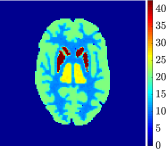

Figure 4, Figure 5, and Figure 6 show the mean images computed over the ten reconstructions obtained by the methods reg-AS-TR, reg-GN, and by the Matlab routine lsqcurvefit implementing a standard Trust-Region-Reflective least-squares algorithm [11, 10]. We used the noise-free IF and the perturbed IF with and of noise, respectively. Figure 7 contains mean and standard deviation values of the kinetic parameters computed over the ten reconstructions and over each one of the four homogeneous regions, for each one of the three noise levels on the IF.

In general, reg-AS-TR and lsqcurvefit seem to provide similar mean reconstructions, although uncertainties associated to lsqcurvefit are significantly bigger. On the other hand reg-GN seems to systematically underestimate the parameter values within region . Furthermore and as expected, for all methods the quality of the parametric reconstructions deteriorates with increasing noise levels; this is more clear from the and parametric images, probably due to the different sensitivities of the data with respect to the model parameters [37]. In reg-GN and lsqcurvefit some artifacts can be observed at the edges of the homogeneous regions, especially around region and region , whereas the effect of regularization in reg-AS-TR results in a reduced presence of artifacts while the structure of the regions is preserved. This general trend is confirmed by the error-bar plots of Figure 7. Finally, the frames in Figure 8 corresponding to reg-AS-TR show a significant improvement of the image quality with respect to what is provided by the other two approaches.